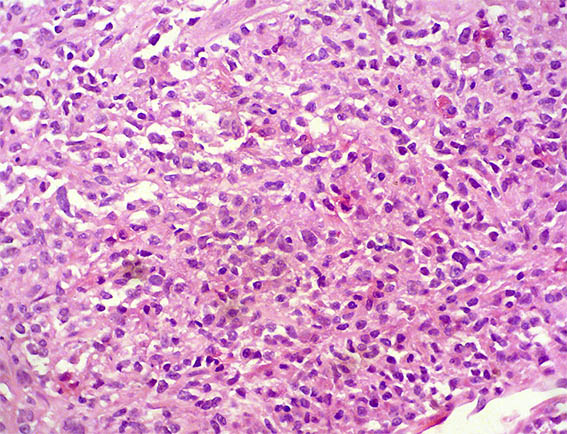

A renal allograft biopsy was done, see the images.

Figure 1. H&E, X40.

Figure 2. H&E, X100.